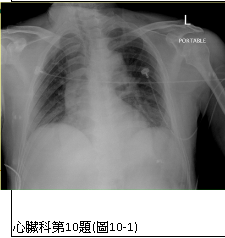

10. 病人62歲男性,於9月4月3:30AM因突發性心胸前區疼痛一個小時而求救急診,時伴有冷汗、臉色蒼白。時,血壓,135/82;心跳,76/min;呼吸,18/min;體溫,35.9度;理學檢查並無重大異常。病人有高脂血病史,Statin治療中。其胸部X光、心電圖及心肌酵素檢查,如圖10-1、圖10-2、圖10-3所示。請問本病人之冠狀動脈阻塞病變最可能的位置是: (A) 左主幹 (B) 左前下行枝 (C) 左迴旋枝 (D) 右冠脈枝 (E) 正常冠狀動脈